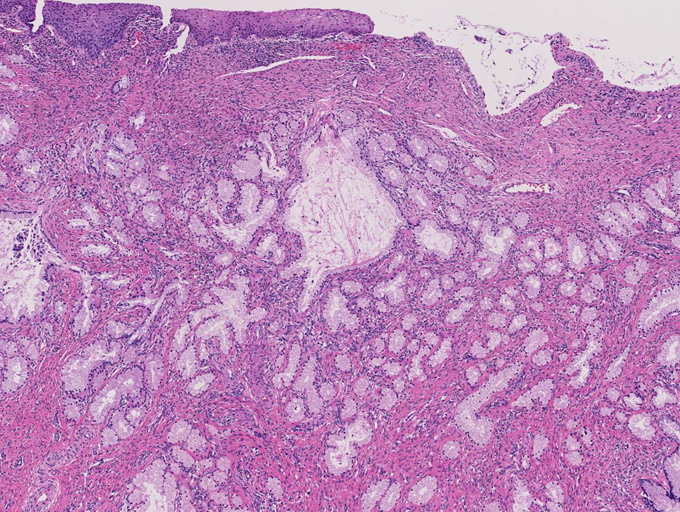

増生腺管上皮の細胞質は淡明ないし淡好酸性で, 核は小型で基底側に配列し、明らかな異型や重層化, 核分裂像を認めない。

腺管が破綻し, 間質への粘液逸脱と、それに対する間質反応も認めるが, この部分でも細胞異型は見られない。

しかしながら完全に異型がないとはいえず分葉構造を保持しているものの上皮の内腔への乳頭状増殖や重層化, 軽度から中等度の核腫大, クロマチン増加, 核分裂像をしめす腺が認められる---> with atypia

間質の一部には炎症細胞浸潤がめだつ。間質浸潤を疑う「折れ釘-->いびつなおれ釘のようなねじれた--」のような不整な形態の腺管は認められない。